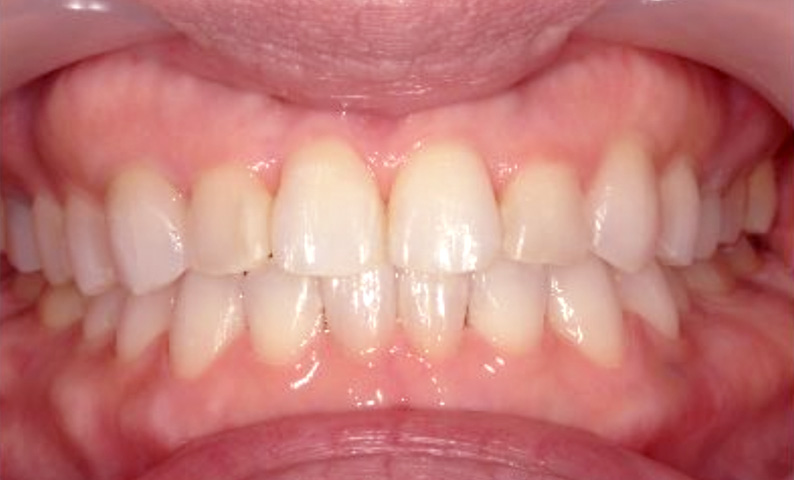

症例_002 下顎だけの部分矯正

治療期間:6ヶ月金額:21万円+税女性前歯のデコボコ下の前歯だけ

| Before | After |